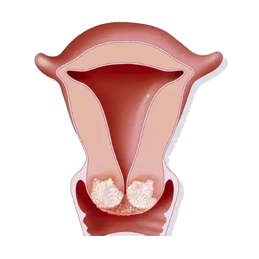

Ή”Ι§Α© «÷ΗΖΔ…ζ‘ΎΉ”Ι§ΒΡΕώ–‘÷ΉΝωΘ§Ήν≥ΘΦϊΒΡ «Ή”Ι§ΡΎΡΛΑ©Θ®Endometrial carcinomaΘ©Θ§ΥϋΤπ‘¥”ΎΉ”Ι§ΡΎΡΛΒΡœΗΑϊΓΘΉ”Ι§Α©Ω…“‘”ΑœλΉ”Ι§ΒΡ≤ΜΆ§≤ΩΖ÷Θ§Αϋά®Ή”Ι§ΧεΘ®Ή”Ι§…œ≤ΩΘ©ΚΆΉ”Ι§Ψ±Θ®Ή”Ι§œ¬≤ΩΘ©ΓΘΉ”Ι§ΧεΑ© «Ήν≥ΘΦϊΒΡάύ–ΆΘ§’ΦΥυ”–Ή”Ι§Α©≤ΓάΐΒΡ‘Φ90%ΓΘ‘ΎΡ≥–©«ιΩωœ¬Θ§Ή”Ι§Α©ΒΡ‘γΤΎΩ…ΡήΟΜ”–Οςœ‘÷ΔΉ¥Θ§“ρ¥ΥΥϋ≥Θ≥Θ‘ΎΧεΦλΜρΦλ≤ι÷–ΖΔœ÷ΓΘ